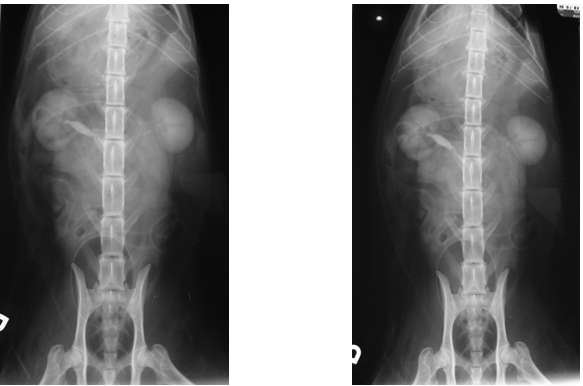

Case Chewbacca

Discuss this case?

–visible on the lateral and VD views

–visible at different time points during the study